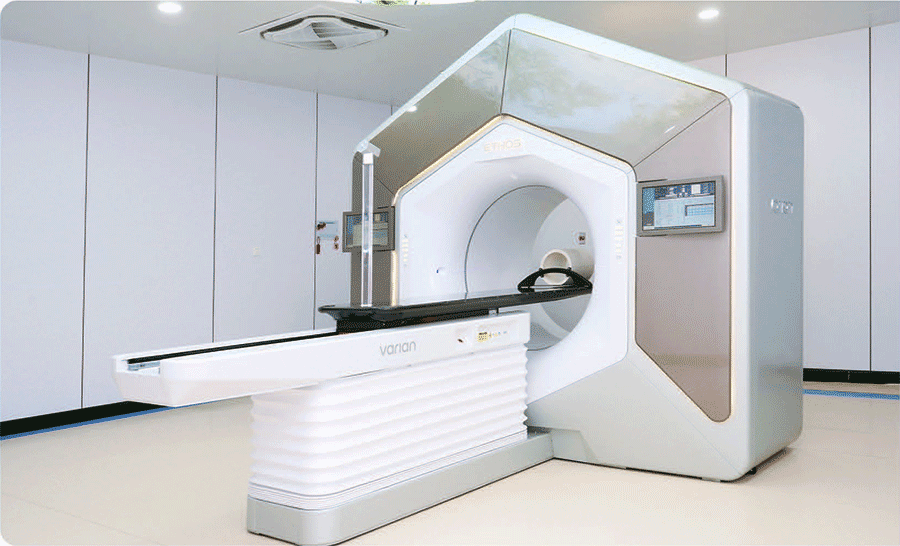

What is the Ethos Linear Accelerator?

The Ethos system imported by our hospital is the world’s first online adaptive radiotherapy system based on artificial intelligence technology. It builds upon conventional linear accelerators by incorporating cutting-edge technologies such as artificial intelligence, multimodal high-definition imaging, efficient imaging scanning, and online quality control systems, enabling efficient online adaptive radiotherapy.

Ethos, installed in September 2022, radiology license obtained on April 7, 2023